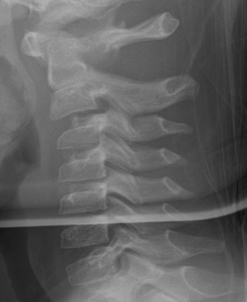

4. Anterior wedging of C3 (or C4)

Anterior wedging of the C3 vertebral body, and less often, C4, is common in children up to the age of 12.5 Cervical vertebral bodies are oval in infancy and become more rectangular with age. However, in C3 and less often C4, wedging can persist. A hypothesis as to why this occurs in some children is that chronic, exaggerated hypermobility normally seen in childhood causes repetitive impaction of the vertebral body of C3 by C2, resulting in a subclinical insult that could impair normal ossification of cartilage at this site. The difference between anterior and posterior vertebral body height must be <3-mm to be considered normal.

Figure 5: Normal anterior wedging of C3